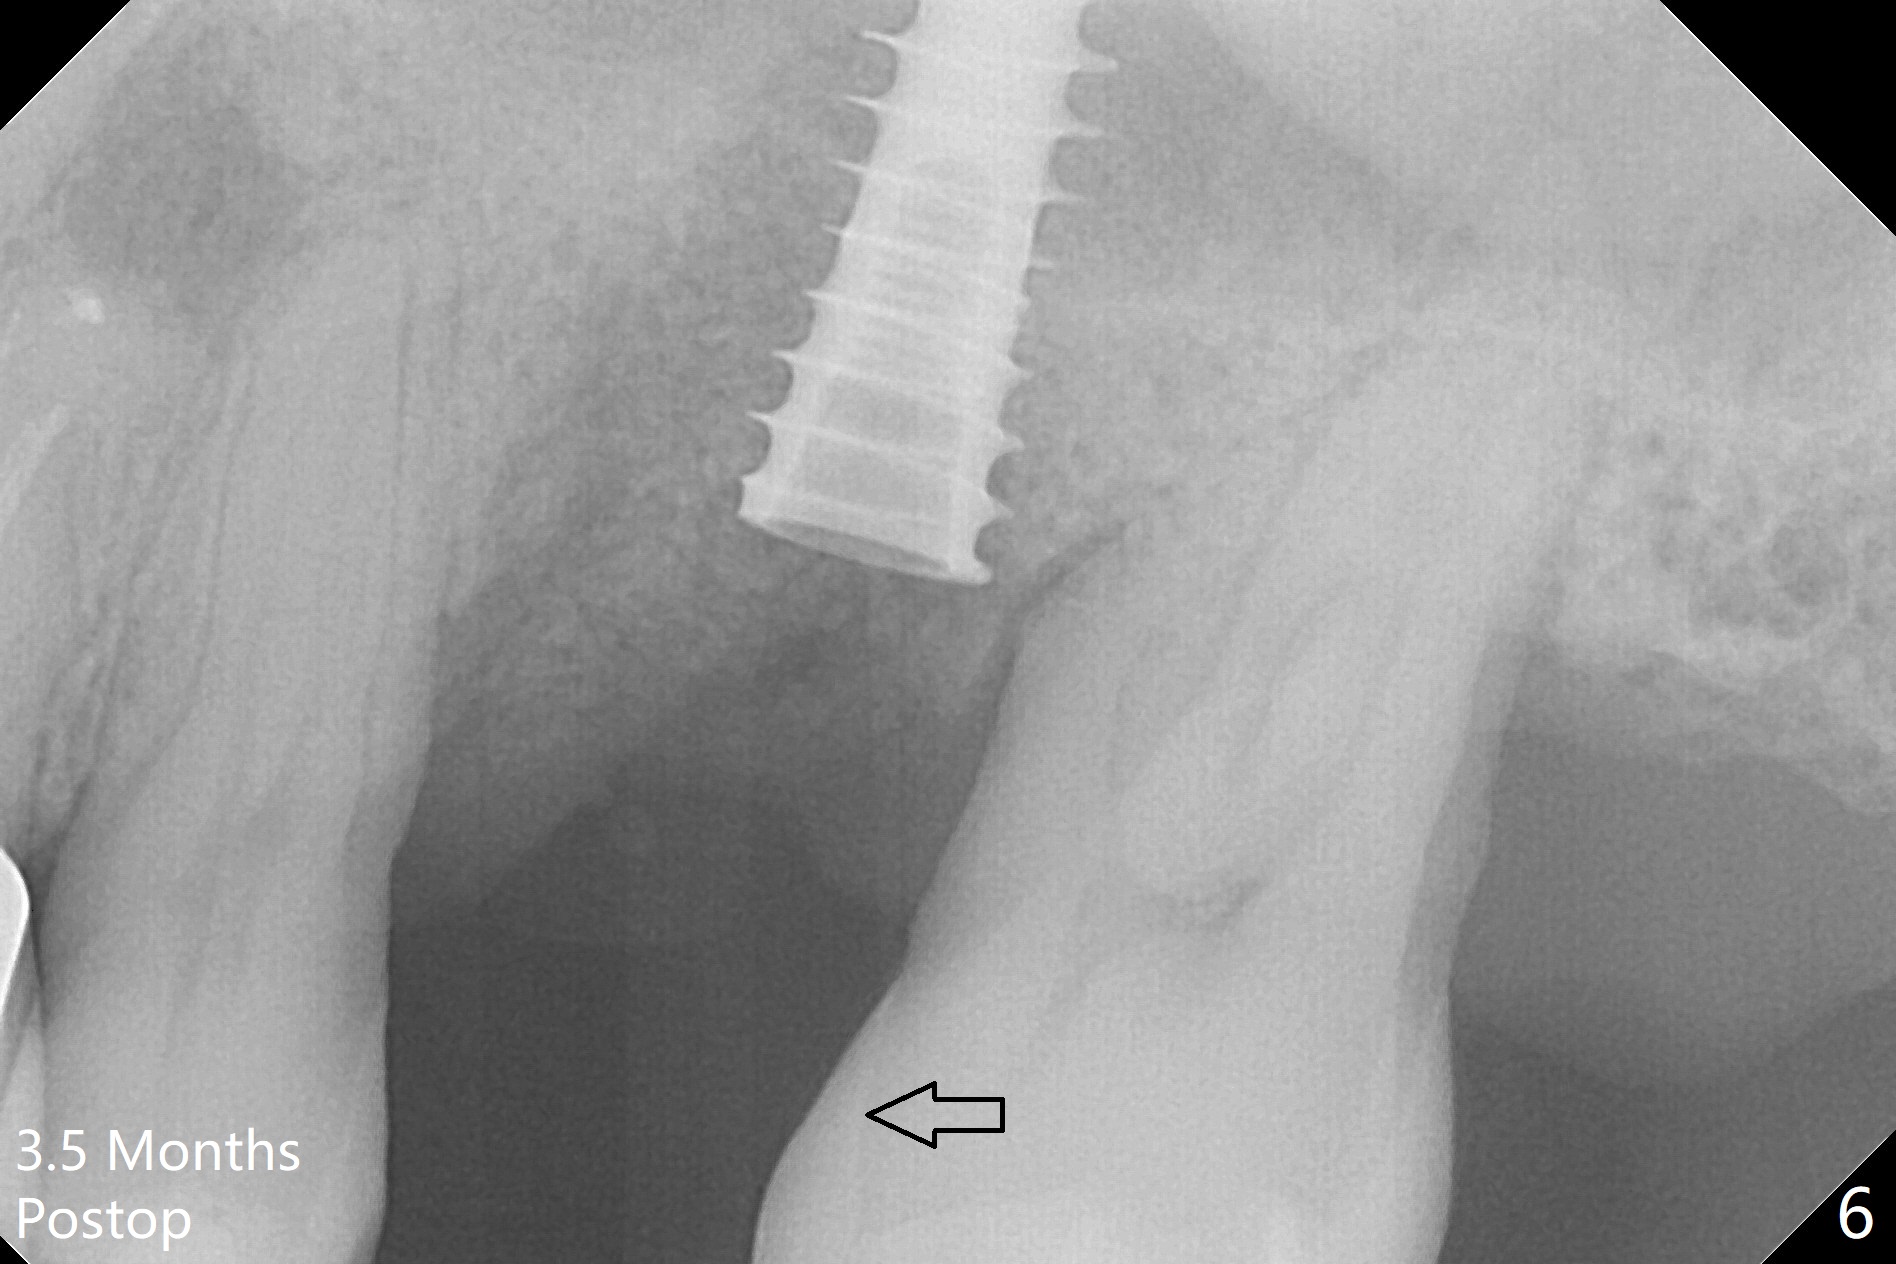

Osteotomy is initiated with Magic Split and 3 mm Magic Expander (ME, flapless) nearly 3 months post socket preservation. To improve the trajectory, the ME is redirected (Fig.1 red line). After use of 3.8 mm ME, Vanilla Graft is placed in the buccal and mesial aspects of the osteotomy. Following reuse of 3 and 3.8 mm MEs, a 4x11 mm dummy implant is inserted with stability (Fig.2 (*: allograft)). More of allograft is placed prior to placement of 5x11 mm IBS implant (Fig.3,4 (~30 Ncm)). The latter is placed palatal. Last the allograft is placed palatal. A 5x4(2) mm abutment is placed to hold periodontal dressing in place. When the ridge is narrow, the implant should be small; 4 mm probably the most appropriate in this case. There is a buccal gap 2 weeks postop (i.e., after dislodgement of periodontal dressing, Fig.5). The implant and abutment appear to be loose ~ 1.5 months postop. The pair abutment is changed to a healing one (5x3mm). The implant seems to be osteotointegrated 3.5 months posotp (Fig.6). Because of the mesial shift of the tooth #15 (Fig.6 arrow (6 months post #14 extraction; anterior open bite)), an angled abutment (5x4mm, 15 degree) is used (Fig.7). Limited orthodontic treatment has to be initiated because the mesially shifted #15 has no occlusal contact mesially (Fig.7 *). A provisional is fabricated with light supra-occlusion. A separator is placed between #14 and 15. Once a space is created in a week, acrylic is added to the distal surface of the provisional and the separator is re-used. In fact the implant is found to be unstable 4.5 months postop (Fig.8,9). The palatal (P) plate is thin and incomplete. The provisional is reduced infraocclusal. Two months the implant remains unstable and is removed.